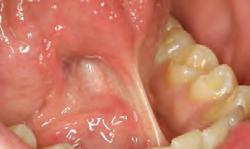

1. Subgingival preparation with bleeding. BLEEDING HEMOSTASIS

2. Scrub Astringedent™ X hemostatic firmly against bleeding tissues with Metal DentoInfusor™ tip.

CLEANING/TESTINGDISPLACEMENT

3. Firm air/water spray removes residual

and tests tissue for quality, profound hemostasis.

Remove

4. Soak Ultrapak™ knitted cord in Astringedent™ X hemostatic, pack, and leave for 5 minutes.